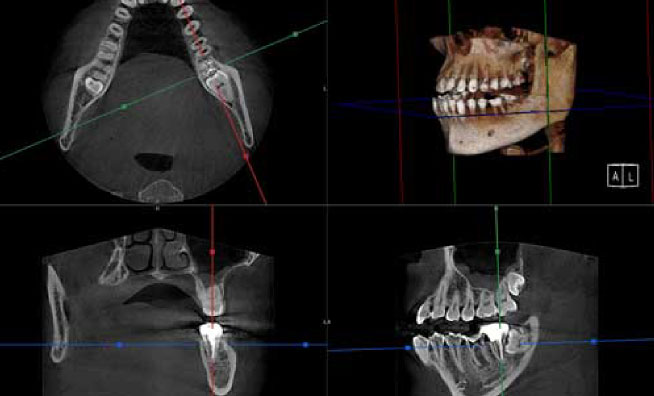

尼崎市ほほえみ歯科では、インプラント治療をはじめ、根管治療や親知らずの抜歯、矯正治療など、正確な診断が求められる治療においてCT撮影を積極的に取り入れています。

通常のレントゲンとは異なり立体撮影が可能になるため、顎の骨の形や歯根、神経の位置といったデータも取得できます。歯や骨の状態をさまざまな角度から把握できるため、得られる情報量が多く、より精度の高い診断につなげることができます。